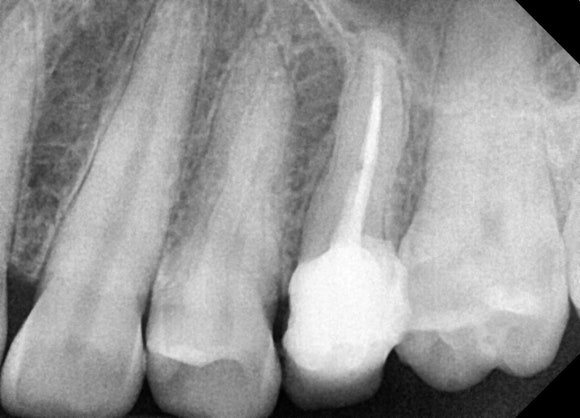

20250411

치아 머리 부분이 까맣게 보입니다.

충치 때문에 치아가 녹아서

텅 비어있기 때문입니다.